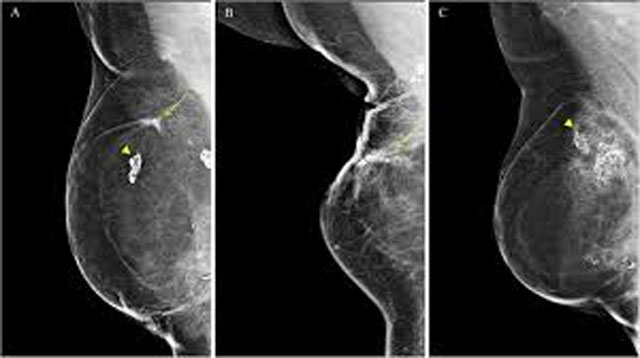

The sustainable approach included the use of indocyanine green dye for sentinel lymph node biopsy, local anaesthesia with intravenous sedation, measures to reduce medical waste, reusable gowns, drapes and surgical instruments, and proper segregation of non-infectious plastic waste.

In terms of surgical outcomes, sentinel lymph node detection rates remained high. Identification reached 100 per cent in the technetium-99m group and 94.1 per cent in the indocyanine green group, indicating comparable clinical effectiveness.